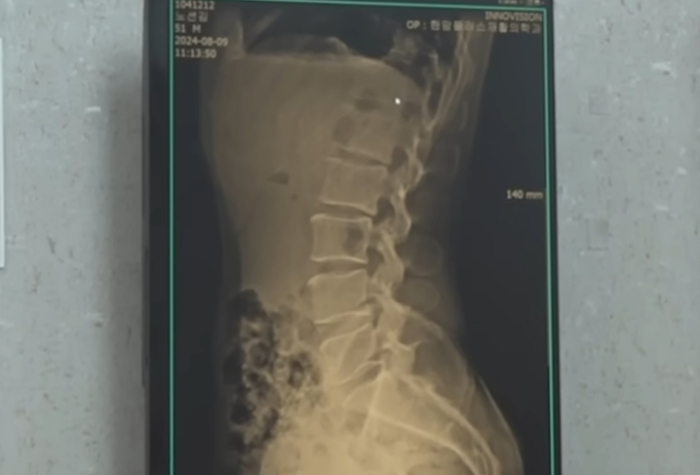

다행히 션은 모든 검사에서 별다른 이상이 발견되지 않았다. 특히 그동안 우려를 모았던 허리와 무릎 상태는 10~20대 못지않은 것으로 확인됐다.

재할의학 전문의 김창원 대표원장은 "허리가 완벽한 C자를 그리고 있다. 근육이 못 받쳐주면 사람이 일자로 서게 되는데 이 나이(50대)에 이 정도 곡선을 그리는 사람은 거의 없다"고 밝혔다.